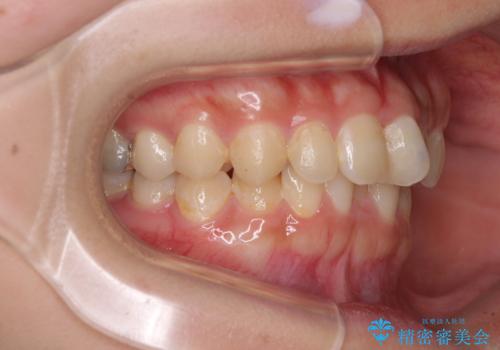

- 前歯のデコボコと深い咬み合わせを改善したいとのことで来院された患者様です。

奥歯の咬み合わせは上顎に対して下顎が後方位にあり、上顎前歯で下顎前歯が隠れるような典型的な過蓋咬合です。

補助装置を用いて上顎大臼歯を後方に移動させながら、ワイヤー装置で歯列を整えて深い咬み合わせを挙上することとしました。